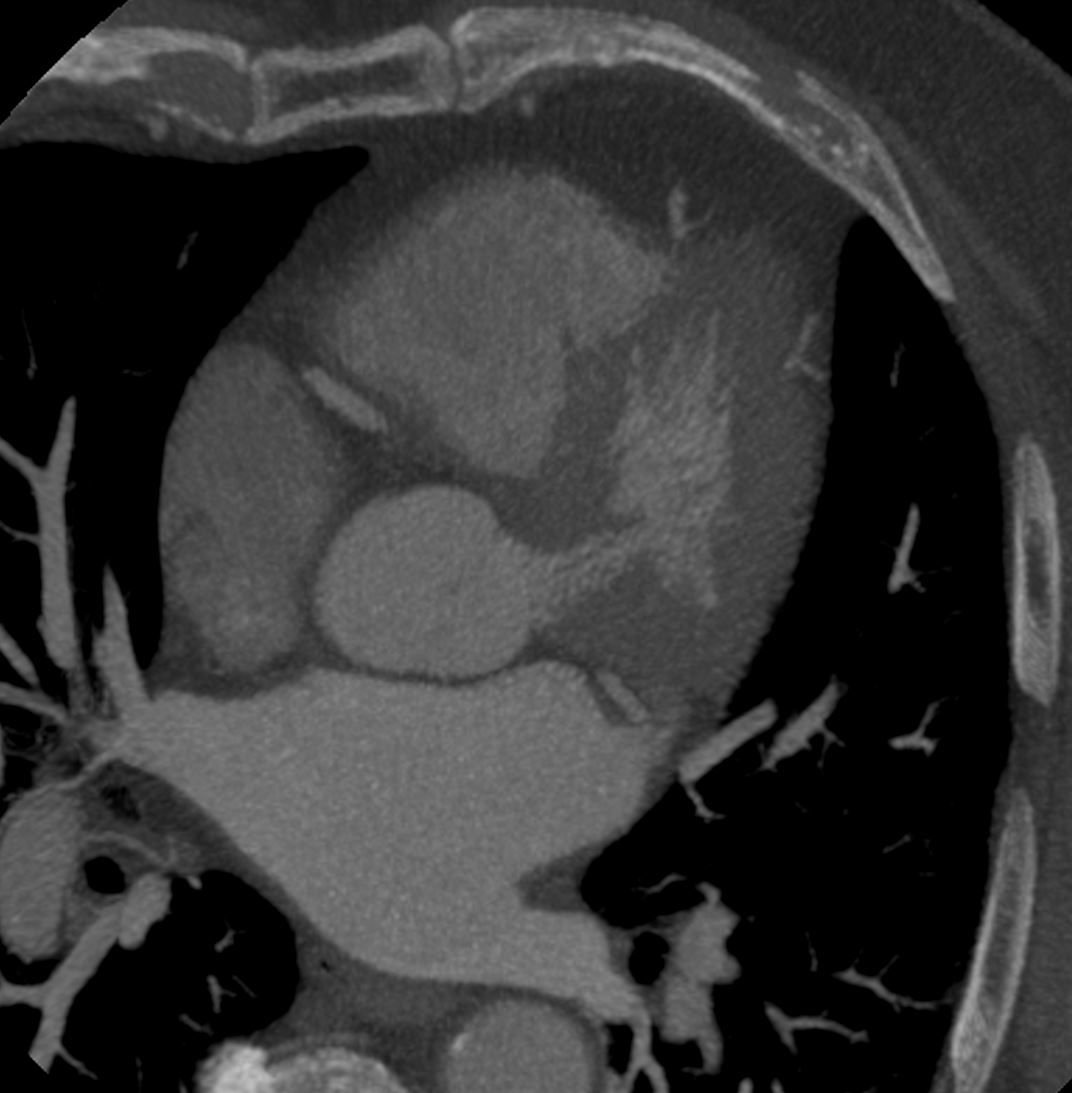

Case: Elderly male with chest pain, palpitations, and mild increase in troponin.

What most likely represents the imaging finding?